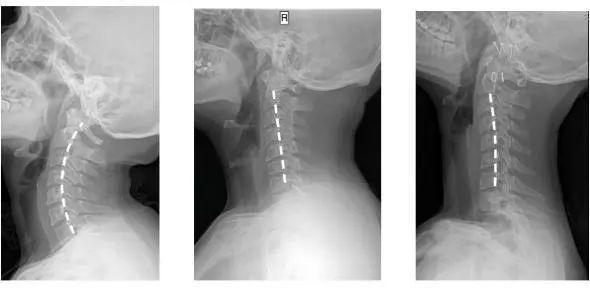

人正常的颈椎是有弧度的

大约是前凸30-45°

但随着颈椎长时间承受着巨大压力

过于疲劳状态

于是弧度就

逐渐退化 变直 甚至反弓

第一张为正常生理曲度,第二张曲度变直,第三张是反向弯曲

前凸的颈椎曲度被改变

结果就是引发椎间盘突出

导致对血管和神经的压迫

肩膀和脖子容易酸痛僵硬

这已是颈椎病的初期症状